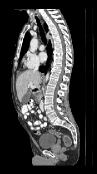

It is prudent to ask whether moving from double precision to single precision on the GPU introduces differences due to rounding. In fact, we observed that this can have an effect (Figure 1). However, it typically only occurs when there are no clear correspondences, such as in regions of the colon with different content, or when the examination table is visible in one of the two scans. In these areas, there is no strong objective function gradient in either direction during optimization, so that numerical differences have a larger impact. However, we argue that if such areas were to be registered accurately, a more elaborate model that accounts for the possible removal of structures would have to be employed in any case.